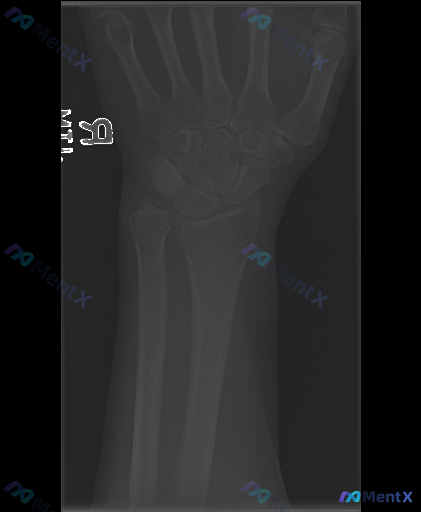

右手腕正位X光片发现异常,除了可见的骨折,还需要警惕哪些方向?

整理到一份右手腕影像学资料及深度评估思路,分享给大家一起讨论。 基本影像表现(右手腕正位X光片) - 骨骼完整性:右侧尺骨茎突处可见明确骨皮质中断,断端有分离移位;桡骨远端关节面、腕骨、掌骨基底未见明确骨折线或骨质破坏。 - 关节与对位:桡腕关节、腕骨间关节间隙清晰,排列大致规则;尺骨茎突骨折处伴随...